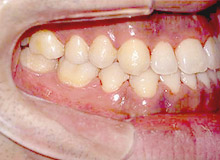

矯正治療前

矯正治療後(完成型)